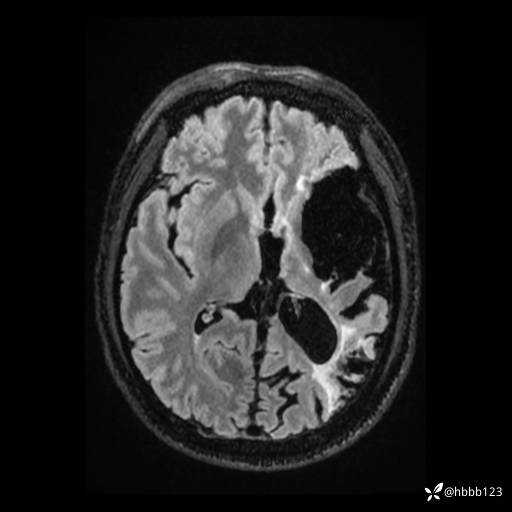

T2: